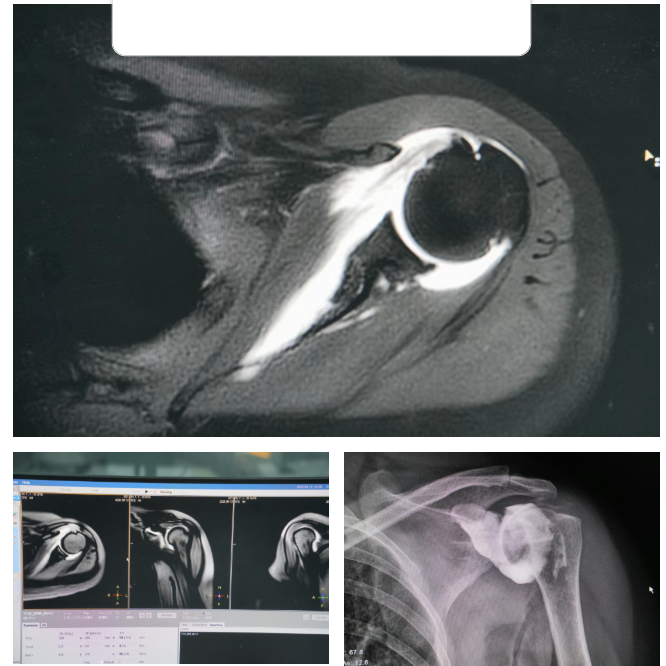

近日,兴安盟人民医院影像中心成功完成兴安盟首例关节磁共振造影(MR arthrography)检查,标志着我院在关节疾病精准诊断领域迈出关键一步,填补了兴安盟地区该项技术的临床应用空白,为当地及周边患者提供了更高效、精准的影像学诊断新选择。

关节MR造影技术主要分为直接法与间接法两类,可根据患者病情灵活选择。其中,直接法通过向关节腔精准注射造影剂,能充分扩张关节囊,大幅提升关节内结构对比度 —— 尤其对肩关节盂唇撕裂、肩袖损伤、关节囊破损等以往难察觉的细微病变,可实现“清晰显影”;间接法则采用静脉注射方式,操作更便捷,适合对关节囊扩张需求较低的病例。

相较于传统MRI或X线检查,该技术的核心优势在于 “精准度升级”:能清晰呈现盂唇、韧带、软骨等关节细微结构,将诊断敏感度与准确性提升30%以上,为临床制定治疗方案提供“可视化依据”。

“不用去外地就能做精准检查,太省心了!”家住乌兰浩特市的张先生是该项技术的首批受益者。此前他因肩关节疼痛反复就诊,常规检查未明确病因,转诊外地又面临时间与经济压力。通过兴安盟人民医院的关节MR造影检查,医生清晰发现其盂唇撕裂,当天便制定了微创手术方案,避免了病情进一步发展。另一位跃进马场闻讯赶来的患者,膝关节疼痛怀疑半月板损伤,需要关节镜进一步检查,此项新技术的开展在造影剂衬托下半月板撕裂一目了然,让影像及临床医生异常兴奋,“侦察兵”明确目标,为下一步治疗方案的设定奠定了坚实的基础。